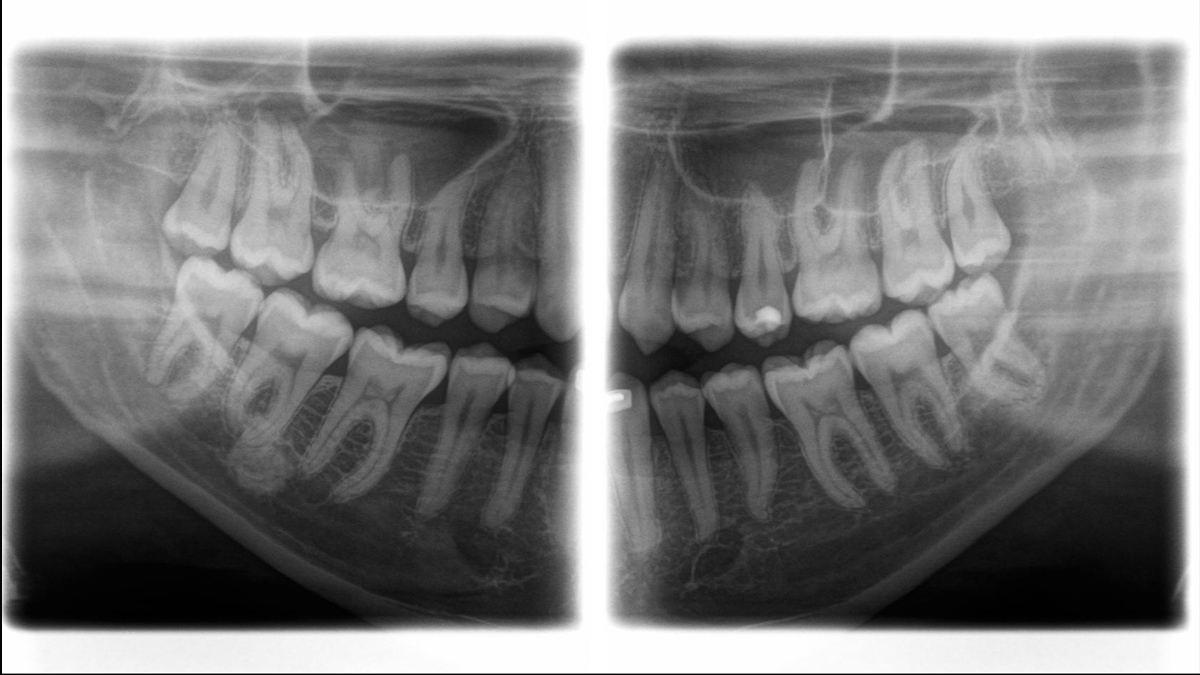

Aunque las radiografías 3D son cada vez más demandadas y existen un gran un número creciente de equipos en consultorios dentales, la imagen 2D sigue teniendo su lugar, en gran medida, debido a su radiación. Las mejoras realizadas en la calidad de imagen hace que las opciones disponibles en tecnología 2D están lejos de haberse agotado. Orthophos SL ha revolucionado la imagen 2D con la introducción del Sensor de Conversión Directa, la tecnología Sharp Layer y la SL interactiva. Experimente imágenes panorámicas como nunca antes.

Galería de muestra de imágenes panorámicas 2D